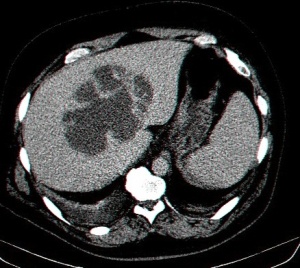

- בטומוגרפיה ממוחשבת של הבטן ניתן לראות גוש בכבד עם פלס אוויר בתוכו ונוזל בעל סמיכות גבוהה (תצלום 40.10). ממצאים אלה הופכים את האבחנה לוודאית.